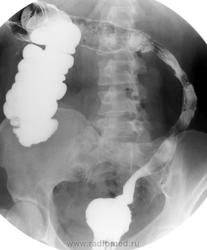

Няк, как Няк.

НЯК не НЯК а на крона похохе...

НЯК, для Крона слишком "длинновато" будет ))))))

Для Крона длинновато,а для НЯКа гладковато..

А что, при НЯКе "свинцовые трубы" отменены?

Няк, как няк с 10-летним стажем.

Отсутствие видимости язв слизистой ставит под сомнение диагноз НЯК.

Стадийность и выраженость клинико-рентгенологических признаков тоже никто не отменял.....

Я понял -необходима скопия.